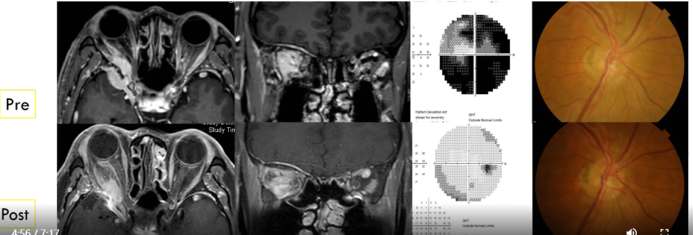

案例分享:一名65岁男性出租车司机患者,右眼视物不清2年。右眼已行白内障手术治疗。眼科检查:视力:右0.15 左1.0。Exo:右17mm 左11mm。术前及行鼻内窥镜肿瘤切除术对比图如下。